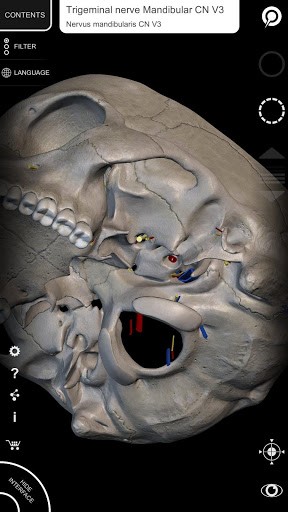

"Anatomy 3D Atlas" vous permet d'étudier l'anatomie humaine de manière simple et interactive.

Grâce à une interface simple et intuitive, il est possible d'observer chaque structure anatomique sous n'importe quel angle.

Les modèles anatomiques 3D sont particulièrement détaillés et avec des textures jusqu'à une résolution de 4k.

• Système nerveux

• En sélectionnant un modèle ou une épingle, le terme anatomique associé apparaît

• Les termes anatomiques et l'interface utilisateur sont disponibles en 11 langues : latin, anglais, français, allemand, italien, portugais, turc, russe, espagnol, chinois, japonais et coréen

• Les termes anatomiques peuvent être affichés en deux langues simultanément